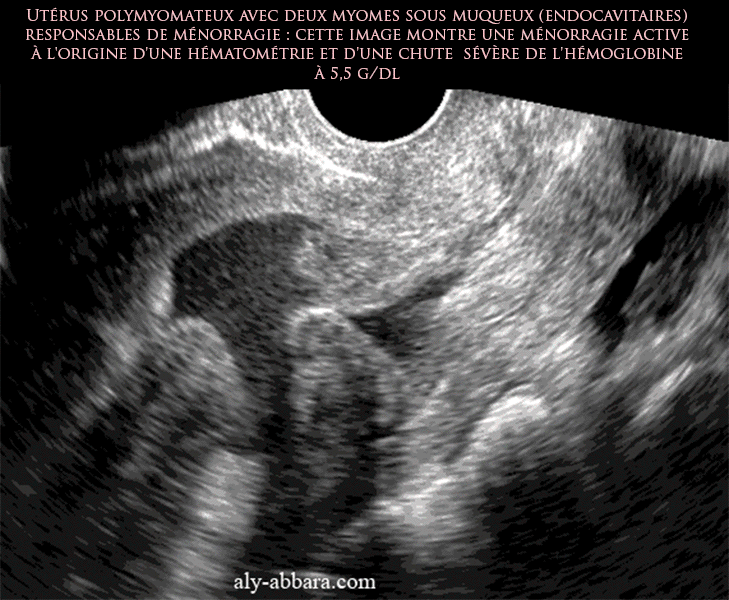

| Utérus polymyomateux avec deux fibromes endocavitaires, sous muqueux, à l'origine d'une ménorragie répétitive. L'image montre une de ces épisodes ménorragique très active à l'origine d'une chute sévère de l'hémoglobine à 5,5 g/dl, ce qui a nécessité un curetage hémostatique de la cavité utérine. |